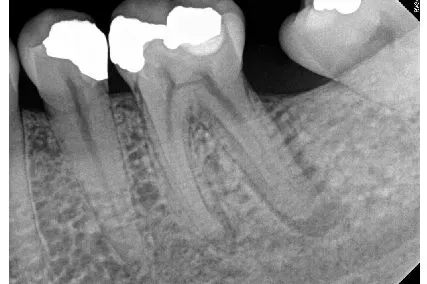

Nhiễu giải phẫu: giải phẫu chồng lên nhau có thể khiến việc hình dung khu vực quan tâm trở nên khó khăn (Hình 5)